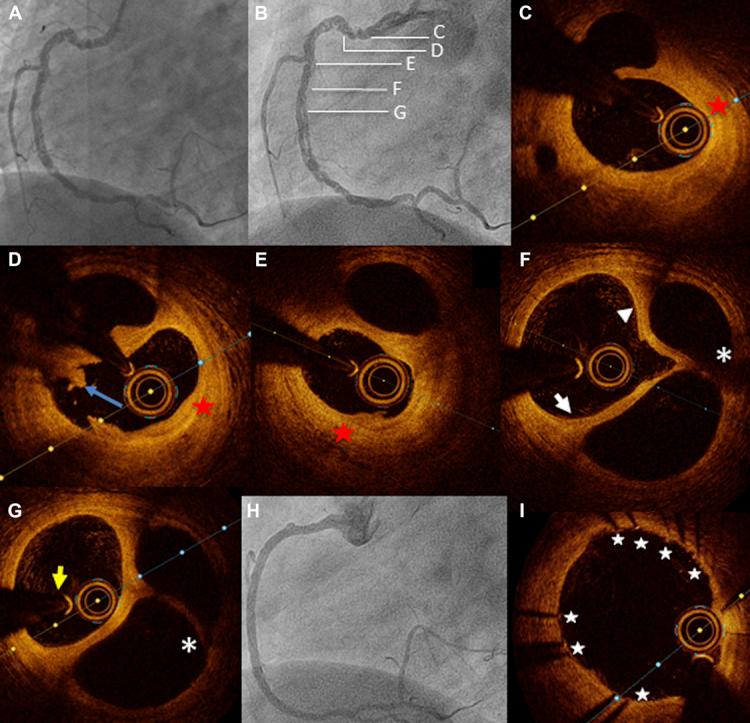

Pathological studies have revealed spontaneous recanalized coronary thrombi as a frequent evolution of coronary occlusions; however, they are poorly recognized on coronary angiography, and the optimal therapeutic strategy for clinical evolution is unknown. We report the role of optical coherence tomography in identifying a recanalized coronary thrombus causing myocardial ischemia after 11 years of follow-up. ().

病理学研究显示,冠状动脉血栓自发再通是冠状动脉闭塞的常见演变过程;然而,冠状动脉造影对其识别较差,且临床演变的最佳治疗策略尚不清楚。我们报告了光学相干断层扫描在随访11年后识别导致心肌缺血的再通冠状动脉血栓中的作用。()